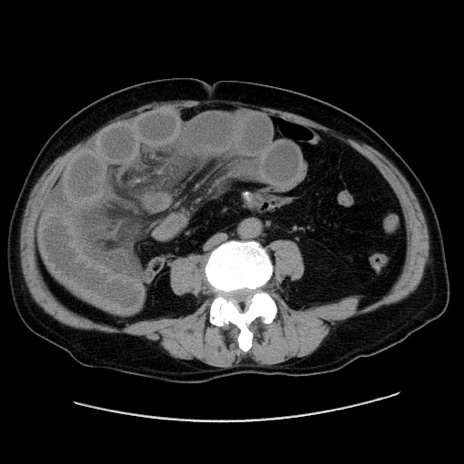

冠状断像

症例30(横断像)

【症例】80歳代男性

【現病歴】約6時間前から臍下部痛が出現。次第に腹部膨隆・背部痛も生じてきたため来院。背部痛の場所は変化しない。

【身体所見】意識清明、BT 36.3℃、BP  131/87mmHg、P 87bpm、SpO2 100%(RA)、臍周囲自発痛・圧痛あり、反跳痛なし、自発痛部位に一致して板状硬あり、腹部膨隆、腸雑音減弱、CVA tenderness両側陰性。

【データ】WBC 19600、CRP 0.33